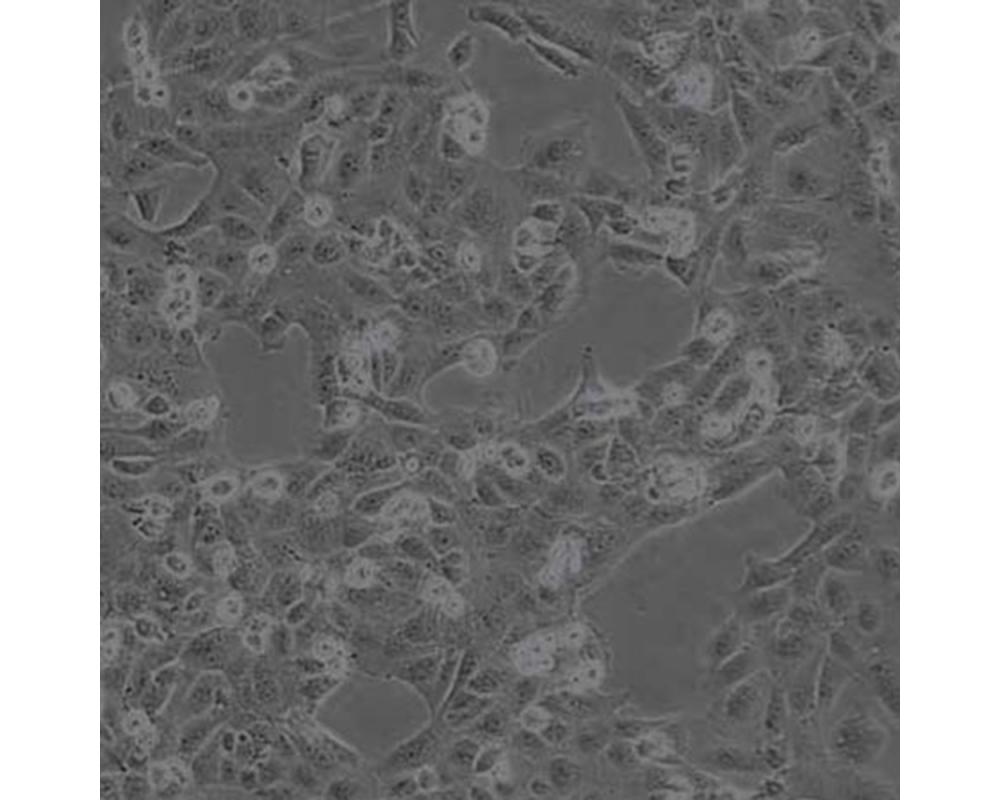

產品名稱 SNU449

中文名稱 人肝癌細胞

組織來源 肝癌;男性

生長特性 貼壁

培養基 1640,90%;FBS,10%;雙抗。

培養條件 Atmosphere: Air, 95%; CO2, 5%。Temperature: 37℃